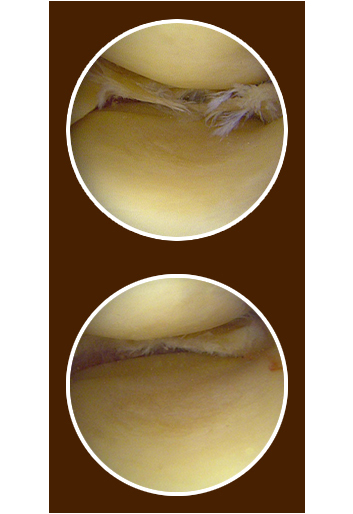

Meniscal repair is an arthroscopic procedure that maintains the entire meniscus by suturing the torn meniscal tissue together.

While meniscal repair can be the best option under the right circumstances, the procedure will depend on the individual circumstance, and the recovery time is longer than resection. The advantage of repair is that the repaired meniscus can protect the knee.